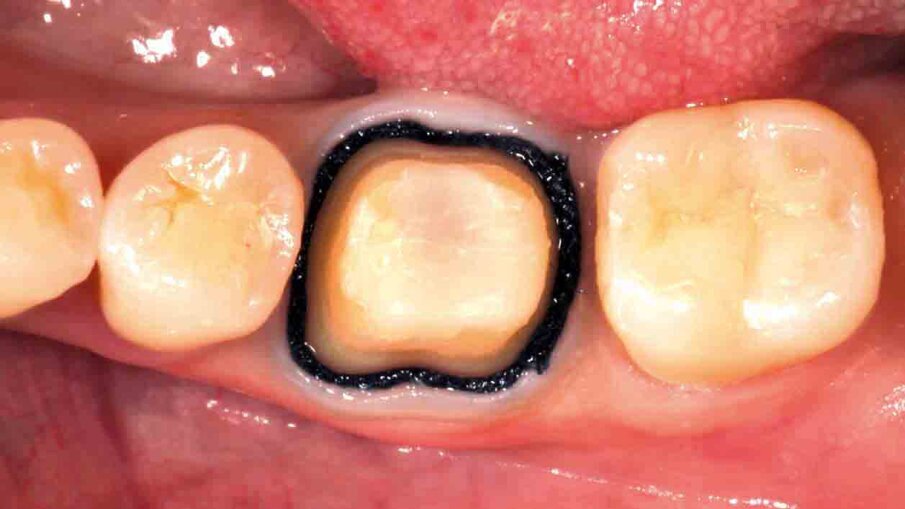

Fig. 1: Initial situation. The failed composite restoration covering a large part of the left mandibular first molar’s occlusal surface needs to be replaced.

Fig. 2: Due to the size of the restoration, the amount of remaining tooth structure might not be sufficient to ensure the required stability for a direct composite restoration.